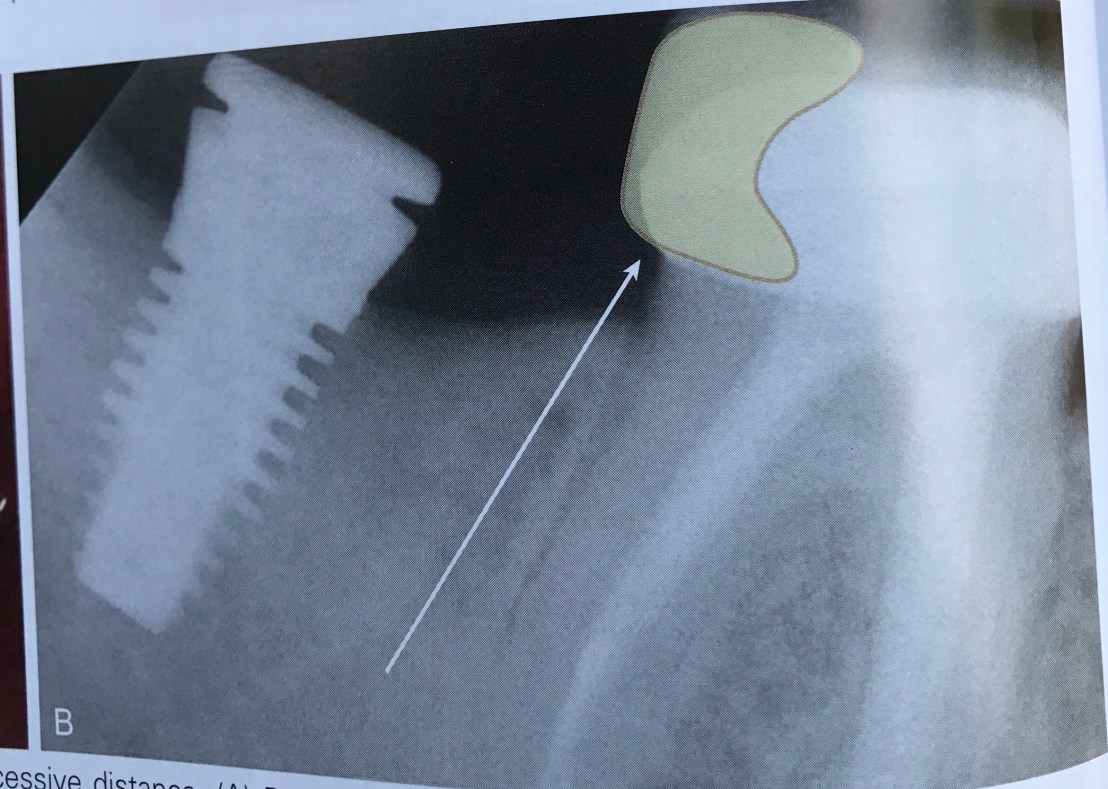

บทที่ 6 ความผิดพลาดจากการวางตำแหน่ง Implant

หรือพูดอีกอย่างคือ การวางตำแหน่งที่ถูกเหมือนการติดกระดุมเม็ดแรกถูกนั่นเองครับ สมมติถ้าเราวางตำแหน่งได้ไม่ถูก จะทำให้ต้อง compromise ตามมาทั้งในแง่ Pros, Perio และการคงอยู่ระยะยาวของ Implant เอง

นอกจากความใกล้กันเกิดแล้ว การวางตำแหน่งที่ห่างกันมากเกินไป ก็เกิดปัญหาได้ดังรูป

เกิดผล 2 อย่างคือ Overcontour ของ crown ทำให้เกิด Perio และ Occlusal table ที่ใหญ่ทำให้เกิด Cantilever ที่เกิดปัญหาทาง Pros และคนไข้จะ complain เรื่อง food impaction อยู่ตลอด

วิธีแก้ไข ถ้าอยู่ติดกับฟันธรรมชาติ คือ เรายอมให้เกิด Cantilever กับฟันธรรมชาติดีกว่าครับ โดยการสร้าง crown ให้ฟันธรรมชาติมี Occlusal table เพิ่มขึ้นแทน